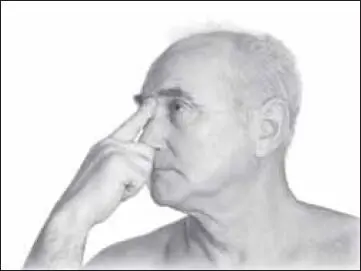

Следующая точка – цин-мин (расположена на внутреннем крае глаза). Затем воздействуем на точку цзя-би (на середине носа, где под пальцами ощущается переход костной ткани в хрящевую). Выполняют самомассаж двумя пальцами (чаще 1-м и 2-м) с усилием 2–3 кг (рис. 126).